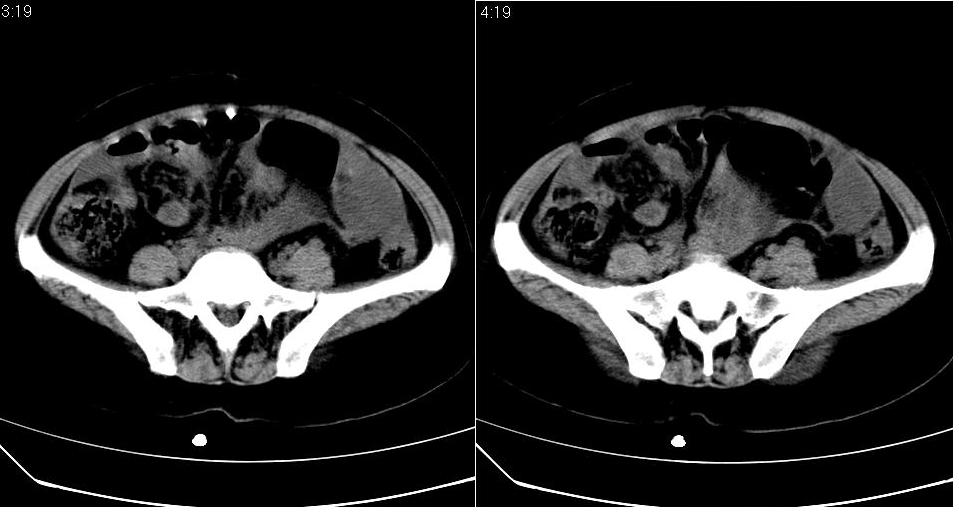

盆腔及腹腔积液,原因待查。

结核性腹膜炎可能,